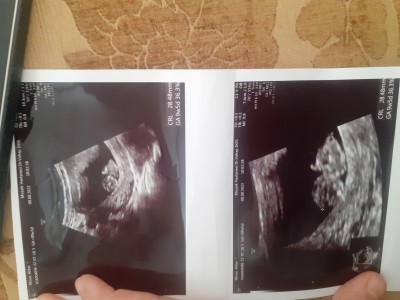

Tecrübeli anneler cinsiyet tahmini yapabilir misiniz :)(resimli)

Sorum yukarda hanımlar

9+5

Resim yok cnm

Ekledim simdi

organları 12de oluşuyor az daha sabr

Daha cok kucuk doktor bile kesin bisi diyemez